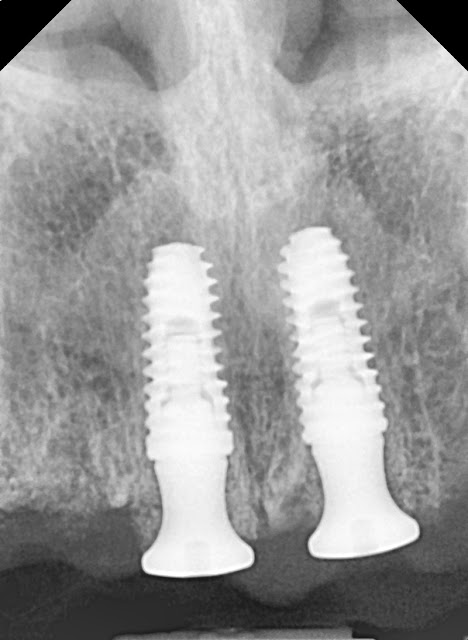

Implants were placed in both central incisor areas due to thin bone in the lateral incisor region on both sides.

A total of four implants were placed to support the planned prosthetic restoration.

Here is the immediate implant placement in the areas of tooth #11

Here is the immediate implant placement in the areas of tooth #21

I paid special attention to the path, considering the anticipation of a screw-type restoration in the future.

I performed bone grafting in the gap area.